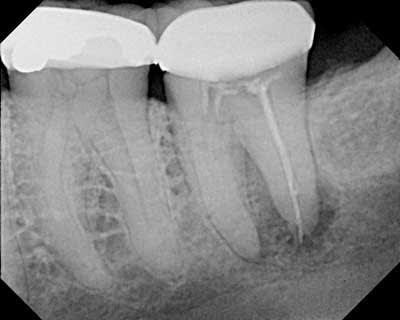

Oui le contrôle qualite c est une bonne chose... La par exemple la radio passe le contrôle qualité... Ouf !